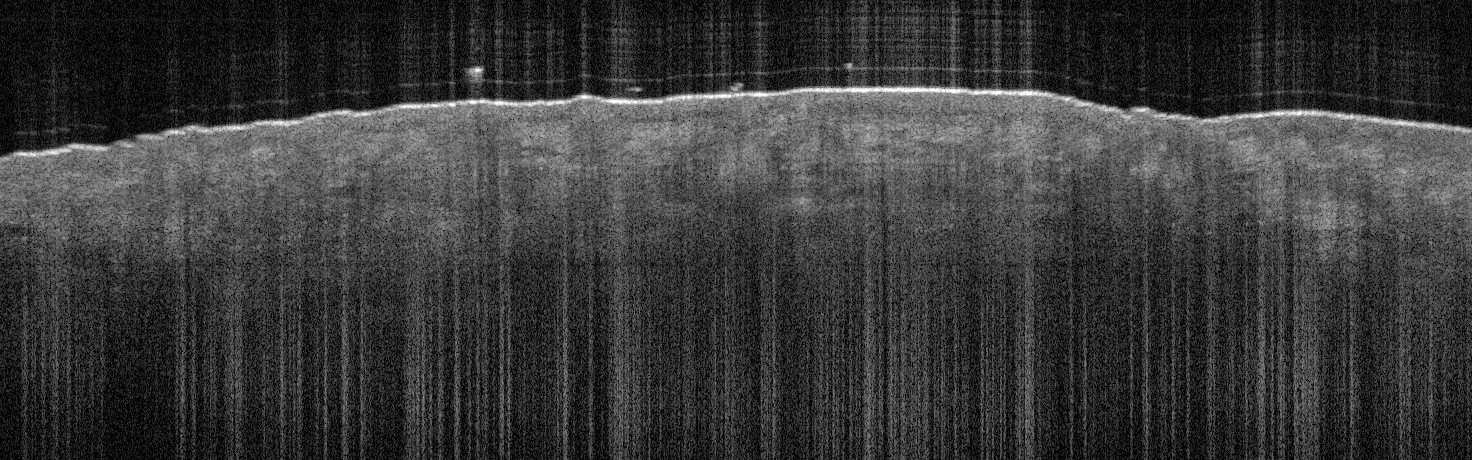

VA118: Nose, Intradermal Melanocytic Nevus

VA118: Nose, Adjacent, Normal